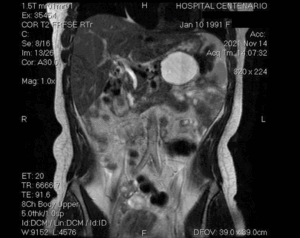

NEOPLASIA QUÍSTICA MUCINOSA DE PÁNCREAS

Ver Caso